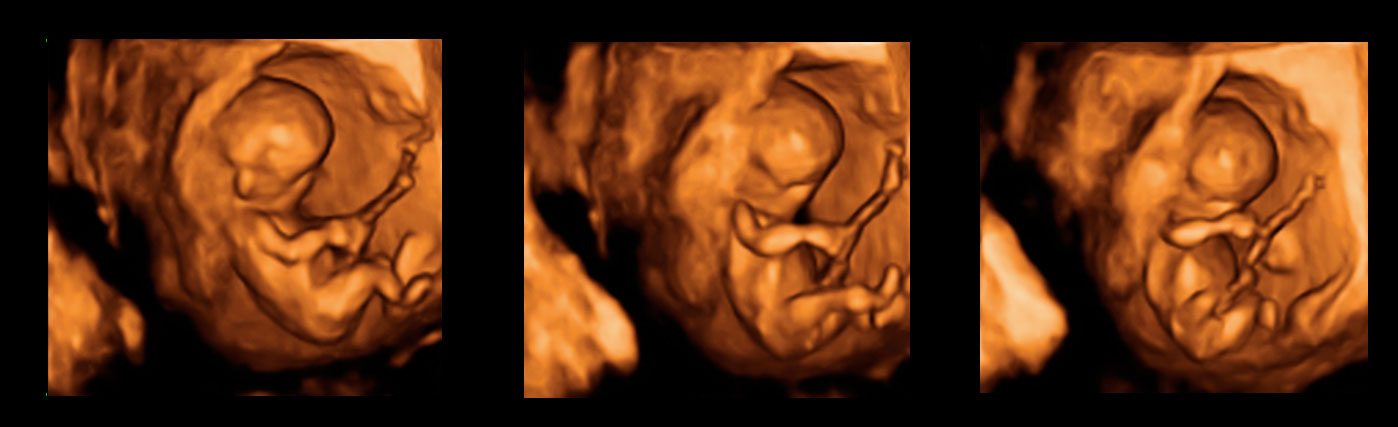

Rotación de trillizos de 10 semanas en ecografía 3D

En esta rotación de una ecografía en tres dimensiones se puede apreciar un embarazo de trillizos de 10 semanas. En el corte del útero en movimiento se pueden adivinar los tres fetos, uno en la parte superior y dos en la parte inferior. También se atisba la membrana de separación entre los grupos de hermanos. Este efecto de imagen poco común lo utilizan los especialistas para ver con más nitidez ciertos aspectos de las ecografías.